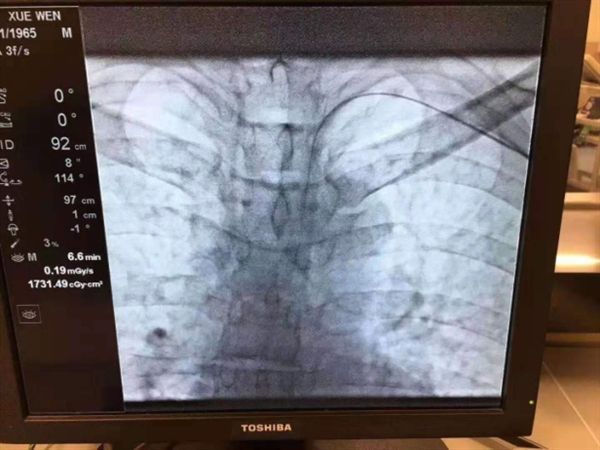

传统的TACE术——经股动脉入路

主流手术方式是通过股动脉穿刺插管至肝动脉,在目标血管处栓塞、注射栓塞剂。其最突出的问题就是患者术后需行股动脉压迫8小时,这很大程度上增加了患者术后不适感(患者躺在床上8小时,不能活动,甚至不能翻身),影响患者术后康复速度,延长了患者住院时间,增加患者经济负担。

创新的TACE术——经桡动脉入路

通过手部的桡动脉穿刺插管至肝动脉,在目标血管处栓塞、注射栓塞剂。其相较于经股动脉入路,有以下优点: